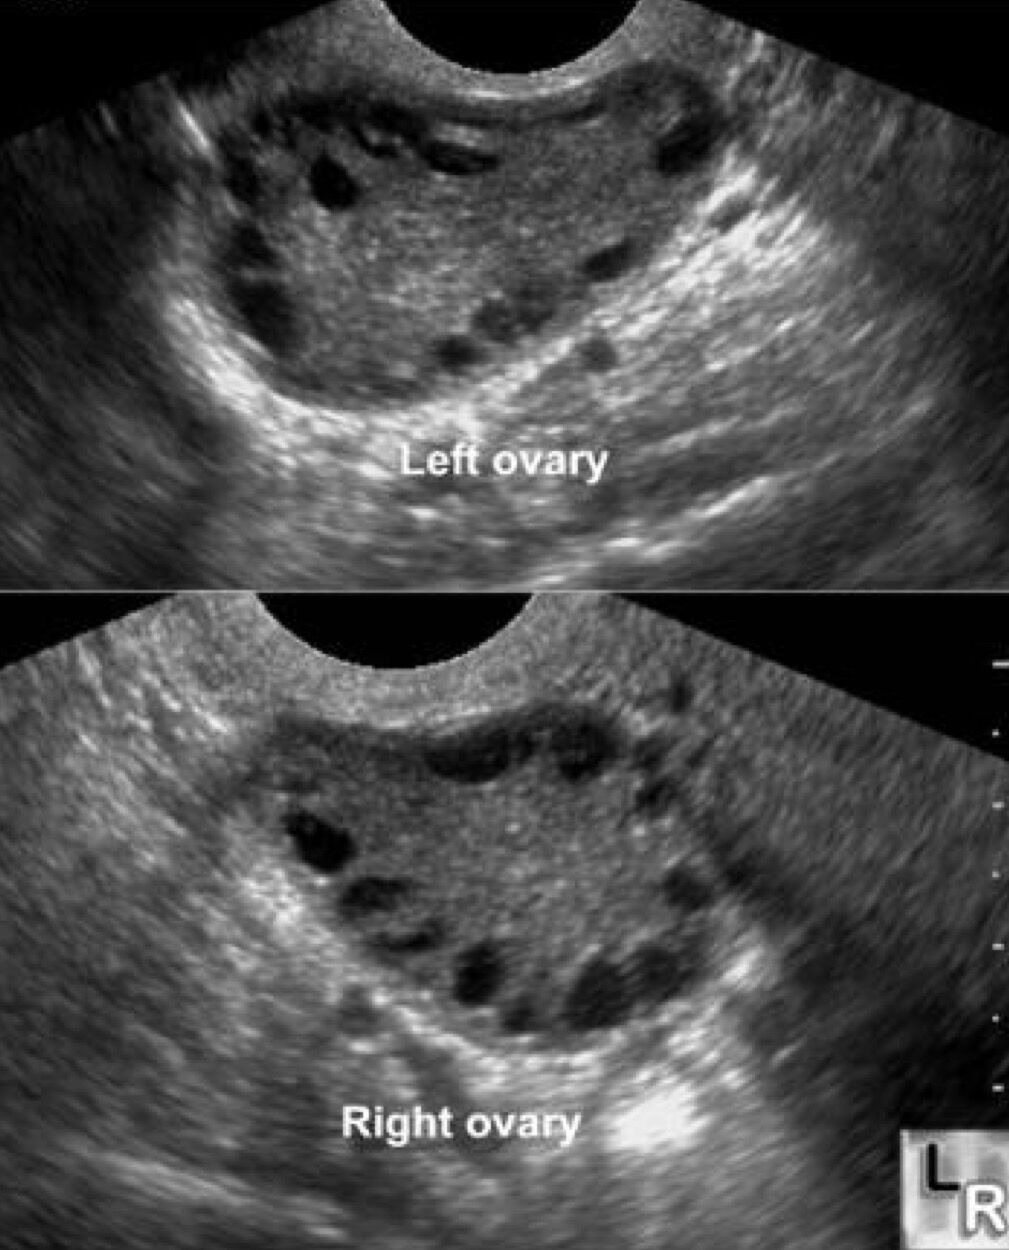

Polycystic ovarian syndrome(多囊性卵巢種):目前機制不清楚,目前認為是濾泡生長受干擾,多發生在第一次estrus cycle

臨床症狀:estrus cycle不規則,分為:

- 過多estrogen➡️慕雄狂:小且多的濾泡造成estrogen堆積。

- 過多androgen➡️雄性化:濾泡無正常功能,缺乏estrogen,造成androgen相對太多

小泡性的濾泡退性:其症狀為許多小型未成熟的濾泡充滿在卵巢的表面,卵巢無法產生正常的濾泡。其臨床症狀為無發情的徵候。治療方法可使用HCG、PMSG或GnRH,但通常效果不佳,故應考慮淘汰。